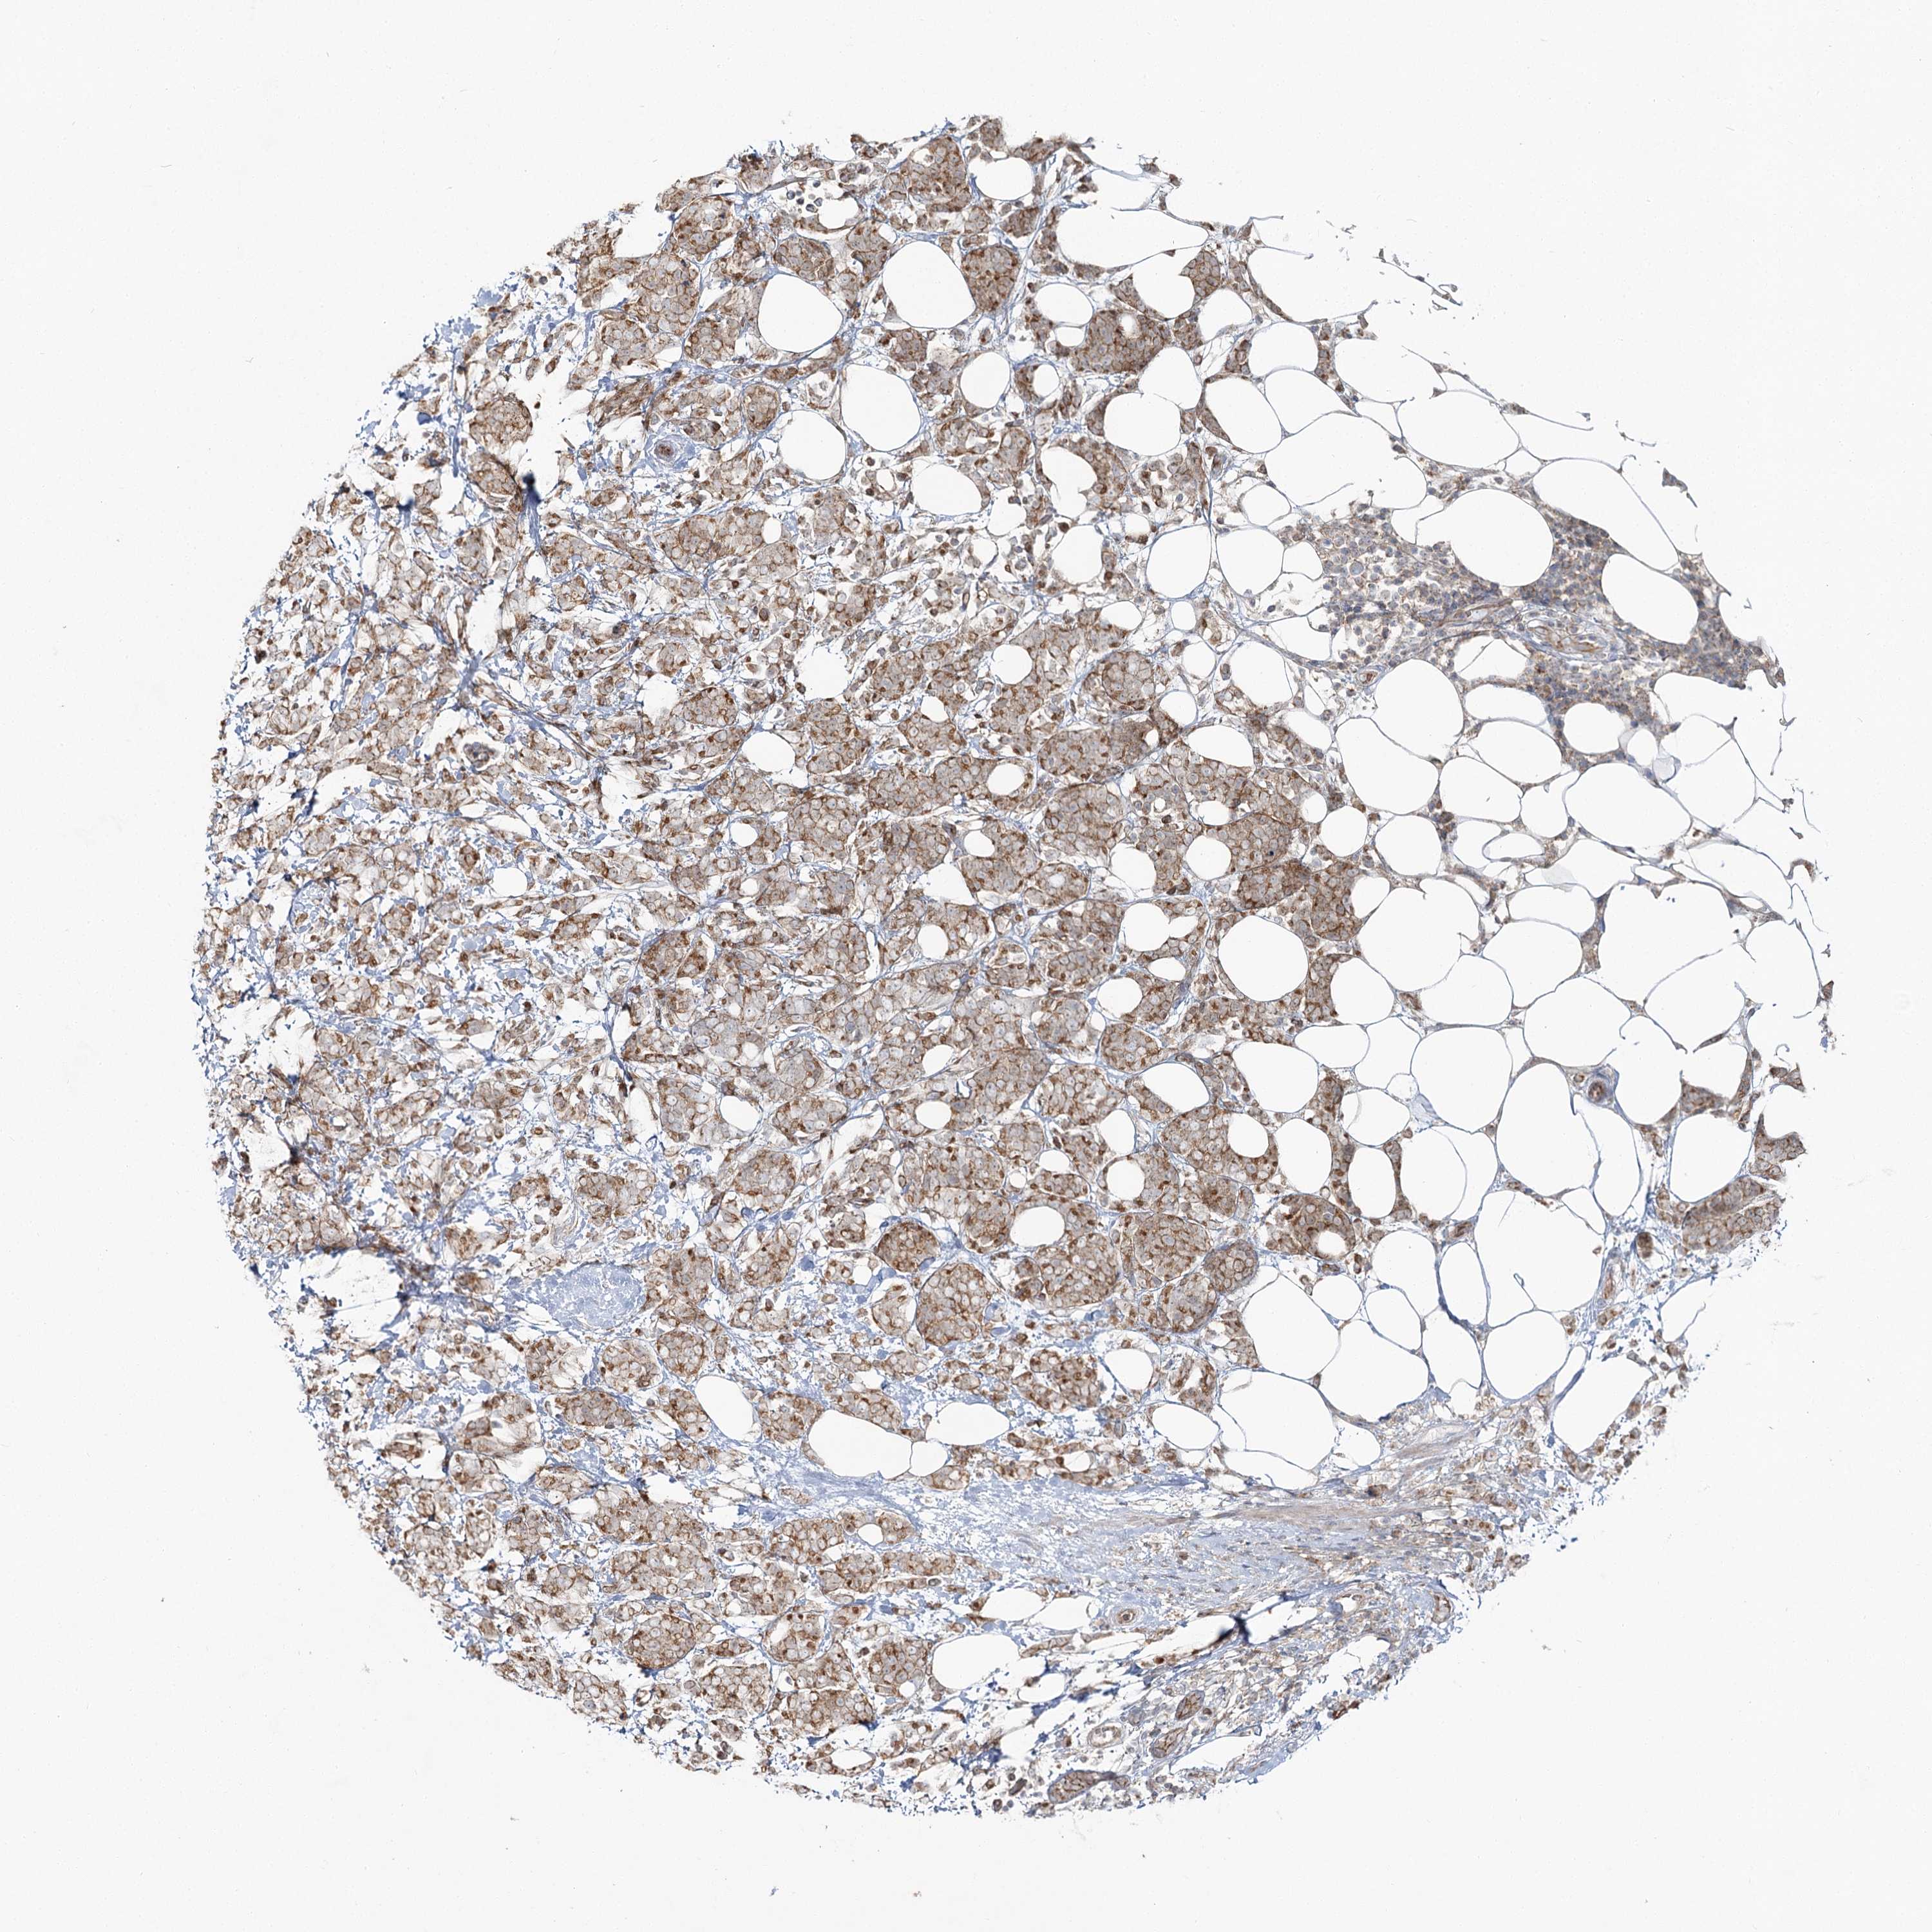

CANCER BREAST CANCER Show tissue menu

BRCA TCGA BRCA VALIDATION PROTEIN EXPRESSION

Breast cancer

Human cancer